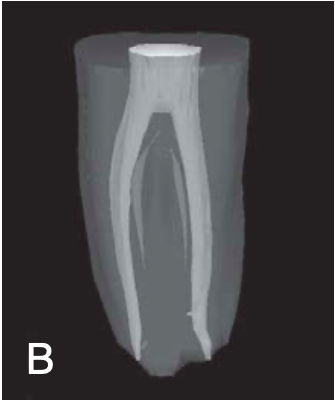

C-shaped roots and canals

most common in MN 2nd molars

also reported in MN 1st molars, MX 1st & 2nd molars, MN 1st premolars

can vary along the root depth so that the appearance of the orifices may not be good predictors of the actual canal anatomy

2 basic types of C-shaped roots and canals

single ribbonlike canal — from orifice to apex (rare)

multiple distinct canals — below the C-shaped orifice (more common)

feature of a root canal obturation

ribbonlike canal space with an arc of 180 degrees or more